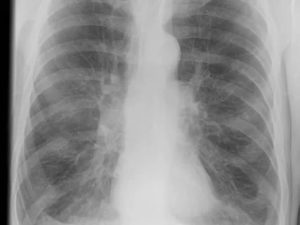

Она расшифровывает рентгенограммы и результаты компьютерной томографии у таких пациентов и рассказывает, что чаще всего пневмонии при COVID-19 двусторонние, затрагивают нижние доли и особенно задние сегменты. О типичной картине таких пневмоний врач рассказала в интервью TUT.BY.

Сначала пациентам стараются сделать рентгенограмму, если по ней неясно, что у человека коронавирус, то обязательно делают КТ.

Если вы посмотрите опубликованные статьи о ПЦР-диагностике, то у таких тест-систем чувствительность около 60%, у КТ она — от 80 до 90% и выше.

Хотя на КТ пневмония при коронавирусе может выглядеть так же, как и другие вирусные пневмонии, но в условиях пандемии мы скорее сделаем вывод, что это коронавирус.

По форме тень на снимке с пневмонией может быть округлой, напоминать веретено, неправильной, в виде кольца. Рисунок тени может быть еле заметный, средней интенсивности, напоминая кость, в случае высокой все напоминает металл. Активность воспаления проявляется интенсивным затенением, границы его могут быть четкими или расплываться, по структуре оно бывает однородным или нет.

Рентгенограмма может стать именно тем исследованием, которое поможет установить истину. Но и оно не всегда информативно, в такой ситуации проводится КТ или МРТ. На ней в различных срезах представлен орган в трехмерном изображении. Как и рентгенограмм исследований может быть проведено несколько с целью контроля лечения.